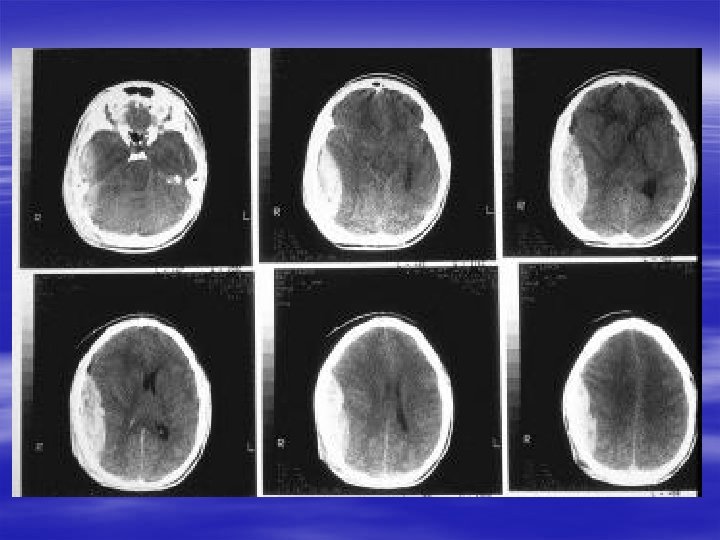

Specific Head Injuries § Epidural Hematoma – Occurs in 0. 5% of all head injuries – Blunt trauma to temporoparietal region – Eighty percent with associated skull fracture – May occur with venous sinus tears – Classic presentation only 30% of the time

Specific Head Injuries § Subdural Hematoma – Sudden acceleration-deceleration injury with tearing of bridging veins – Common in elderly and alcoholics – Classified as acute, subacute or chronic § Acute <2 weeks § Chronic >2 weeks